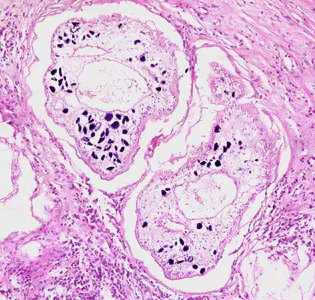

Migrating spargana cause various symptoms depending on the final location in the host. Spargana may locate anywhere, including subcutaneous tissue, breast, orbit, urinary tract, pleural cavity, lungs, abdominal viscera and the central nervous system. The migration in subcutaneous tissues is usually painless, but when spargana settle in the brain or spine a variety of neurological symptoms may occur, including weakness, headache, seizure, and abnormal skin sensations, such as numbness or tingling. If the inner ear is involved, the patient may experience vertigo or deafness. Occasionally, Sparganum proliferum can cause proliferative lesions in the infected tissue, with multiple plerocercoids present in a single site.

Proliferating spargana in lung tissue.